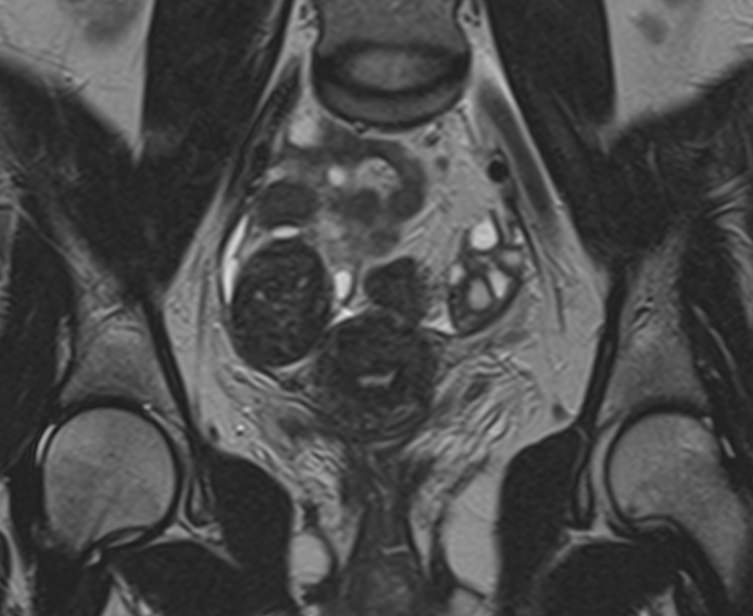

В клинике «Доступная медицина» МРТ яичников выполняется на современном томографе экспертного класса TOSHIBA VANTAGE TITAN 1,5 Тесла, который производит послойное сканирование анатомической области яичников в трех различных плоскостях с последующей цифровой обработкой полученных данных и построением трехмерных изображений исследуемой зоны.

Что показывает МРТ яичников?

На МР-исследовании могут быть обнаружены:

• пороки развития;

• снижение числа фолликулов или их отсутствие;

• функциональность имеющихся фолликулов;

• кисты;

• острое и хроническое воспаление, абсцессы;

• опухолевые процессы.

МРТ яичников: что показывает процедура

• Апоплексию яичника (разрыв придатка, сопровождающийся попаданием крови в брюшную полость и сильным болевым синдромом);

• Новообразования яичников (кисты, фибромы, рак);

• Признаки доброкачественного или злокачественного характера опухоли;

• Врожденные аномалии развития придатков;

• Признаки синдрома поликистозных яичников;

• Вовлеченность в опухолевый процесс соседних органов.